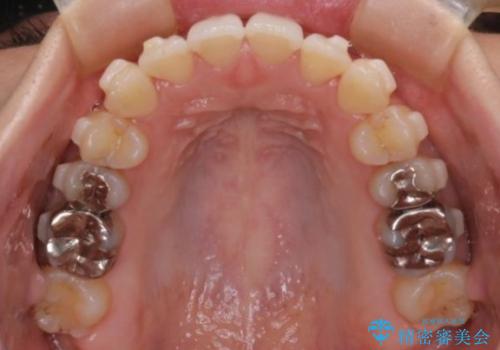

- 前歯のガタガタを主訴に来院された患者様です。

前歯の傾きも少し内側に入るように計画をたて、インビザラインにて治療を行いました。

このぐらいのガタガタであれば、インビザラインで簡単に治すことができます。